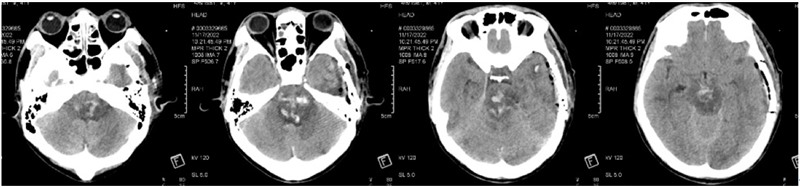

患者姚某某,41岁男性,是家里的经济支柱和精神支柱,患者于11月15日突发意识障碍,呼之不应,伴肢体抽搐,立即送往当地区医院,医院完善头部CT提示“脑干出血”,量约15ml!

术前ct

脑干是人体的“生命中枢”,素有“生命禁区”之称,脑干出血起病急、病情重、进展迅速,出血量超过10ml以上,死亡率几乎为100%。